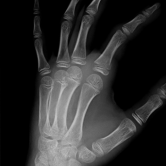

Röntgenbilder